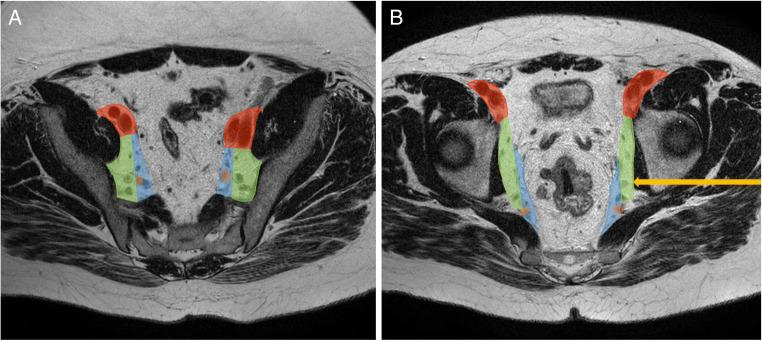

Enlarged lateral lymph nodes (LLNs) are associated with increased (lateral) local recurrence rates. Size and anatomical location should therefore always be reported by radiologists and discussed during multidisciplinary meetings. The objective was to investigate how often LLNs are mentioned in MRI reports in a tertiary referral centre.

A single - centre, retrospective study of 202 patients treated for primary rectal cancer between 2012 and 2020, with at least a T2 tumour located within 12cm of the anorectal junction. The radiology reports were written by 30-40 consultant radiologists. MRI scans were independently re-assessed by an expert radiologist. The primary outcome was how often the presence or absence of LLNs was mentioned in the initial report.

增大的侧方淋巴结(LLNs)与增加的(侧方)局部复发率相关。因此,放射科医生应始终报告淋巴结的大小和解剖位置,并在多学科会议上进行讨论。本研究旨在调查在一家三级转诊中心,放射科医生在 MRI 报告中提及 LLNs 的频率。

对 2012 年至 2020 年间接受原发性直肠癌治疗的 202 名患者进行了单中心回顾性研究,这些患者至少有一处 T2 肿瘤位于肛直肠交界处 12cm 以内。放射学报告由 30-40 名顾问放射科医生撰写。MRI 扫描由一名专家放射科医生独立重新评估。主要结局是初始报告中提及 LLNs 存在或不存在的频率。